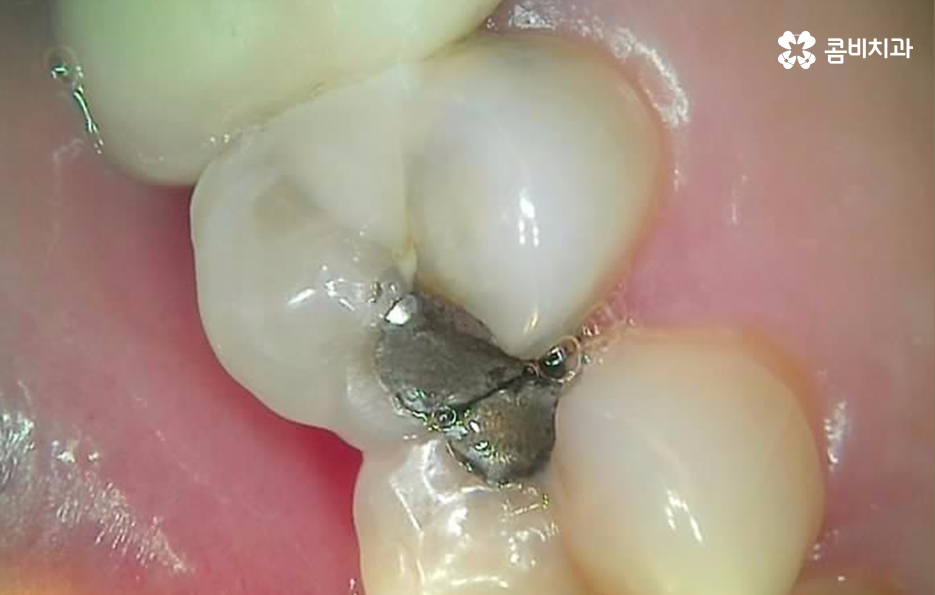

많은 환자분들께서 이미 충치 치료를 했던 부위인데 왜 또 충치가 생길 수 있는지 의아해 하시는 분들도 계실 거예요. 충치 치료를 했던 부위를 살펴보면 보철 재료와 치아 사이에 경계면이 있다는 것을 알 수 있는데요.

충치 치료 후에는 보철물과 치아 사이의 경계선 부분에서 보철물의 접착제가 녹는 경우도 있고 보철물 자체의 손상이 발생되는 경우도 있으며 보철물은 멀쩡하더라도 자연치아가 마모되고 깨지는 등의 문제가 발생될 수 있는데 이때 보철물과 치아 사이에 틈이 발생되면 치아 내부로 세균이 침투하여 2차충치가 발생되는 원리라고 할 수 있어요

이처럼 2차충치가 치아 내부로 진행된 경우에는 치아 구조의 특성상 치아의 겉면에 비해 내부가 좀더 약하기 때문에 충치는 비교적 쉽게 내부로 깊어질 우려가 있으며 신경조직에 손상이 발생한 경우에는 신경치료를 해야 하기 때문에 자연치아의 손상이 그만큼 커질 수 있어요

이러한 문제는 치아 내부에서 발생하기 때문에 눈으로 살펴볼 때는 상태 확인이 어렵고 명동치과 주기적으로 검진을 하지 않는다면 통증을 통해 뒤늦게 문제를 인지하기 때문에 치료 시점도 초기치료는 놓친 경우가 대부분이라 할 거예요